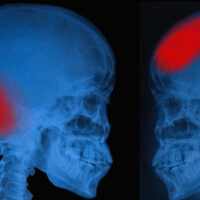

A head injury is any type of damage that occurs to an accident victim’s scalp, skull, or brain. A head injury can range from something mild and temporary to severe and permanent. In the worst cases, a head injury can lead to the death of a victim. Head injuries are either classified as open or closed. An open head injury is also known as a penetrating head injury, where something breaks the scalp and skull of the victim and enters the brain. A closed head injury is one that does not break the scalp or skull but can still cause substantial damage.

Hematoma

A hematoma injury is a clotting of blood outside of the blood vessels and is also known as bruising. However, if a hematoma occurs outside the blood vessels of the brain it can lead to a pressure buildup in the skull that can cause a loss of consciousness or brain damage.

Hemorrhage

A hemorrhage injury occurs when there is uncontrolled bleeding inside an accident victim’s head. Hemorrhage injuries that are in the space between the brain and skull are known as subarachnoid hemorrhages, where a bleeding injury that takes place inside the brain tissue is an intracerebral hemorrhage.